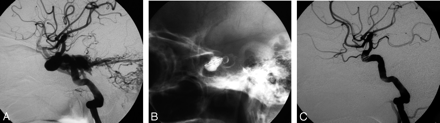

Images of a 40-year-old man with traumatic DCCF. A, Right lateral carotid angiogram shows a residual fistula after 2 detached balloons and 1 coil embolization. B, A total of 1.1 mL n-BCA mixture was slowly deposited to the cavernous sinus in 2 attempts. C, Postembolization angiogram shows total occlusion of the fistula with ICA preservation.